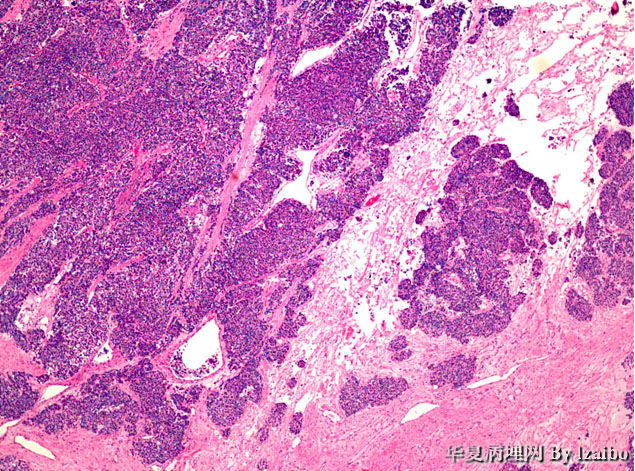

大体标本描述:肿块位于左肾上极,大小为15×9×8.5厘米。切面上,肿瘤为黄色,并具有散落的白色区域和偶尔出血区,没有明显坏死区。肿瘤非常接近血管,但大体上没有侵入到血管壁。大体上可见肿瘤侵犯输尿管和骨盆(图1和图2)。显微图片(图3-7)。

• 病例1-摘自UPMC Web Cases图4

图4